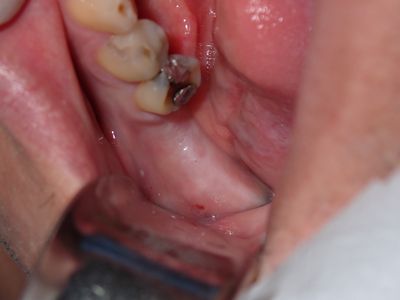

WYu - 36 implant

Loss of lingual bone, osteotomy prepared in ideal position, prepared to about 2.8mm, remainder with combination of densah drills for crestal 1/2 and straumann drills to length. Implant placed with ample bone around it.